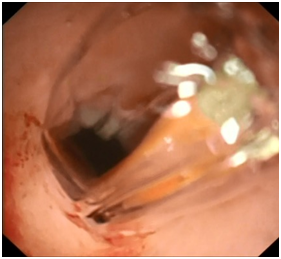

US guided drainage was done for both the ascites and the pancreatic cyst. He was kept NPO, on TPN and given antibiotics and Octreotide. A follow-up CT scan showed persistent pseudocyst but smaller in size (4.3X2.6X1.8 cm) with minimal free fluid in the abdomen, so the drain was removed and he was started on low fat diet which he tolerated well. During follow up after 3 months, the patient was symptomatic complaining of abdominal pain and distension (Figure 2). A repeat abdominal ultrasound showed enlargement of the pancreatic pseudocyst size (5.9X4.6 cm) so he was referred to our hospital for evaluation and possible EUS guided transgastric pseudocyst drainage (Figure 3).

Figure 2A & 2B EUS images of the pancreatic pseudocyst.